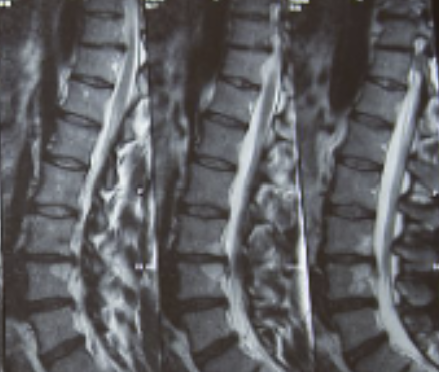

허리디스크는 디스크가 터져서 신경을 누를 경우 생기는 것으로 보통 4,5번에서 많이 발생하고 디스크가 터진 양이 적다면 터진 순간부터 수분이 날아가면서 양이 많이 없어지는데 그렇지 않고 양이 많을 경우 극심한 통증이 생깁니다.

허리디스크를 정확하게 진단하기 위해서는 엑스레이로는 힘들며, MRI를 통해 검사해야 정확하게 볼 수 있습니다.

MRI가 몸에 좋지 않지만 허리 통증으로 엑스레이만 진행 할 경우 오진이 많아 지속적인 통증이 계속 된다면 허리디스크를 의심하고 MRI 검사를 한번 받아보시길 권유드립니다.